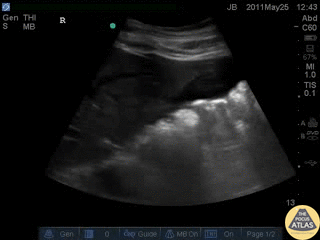

Trauma - Positive FAST - RUQ

Blunt trauma patient with POSITIVE FAST scan. The liver can been seen floating in fluid with adjacent bowel. Dr. Justin Bowra